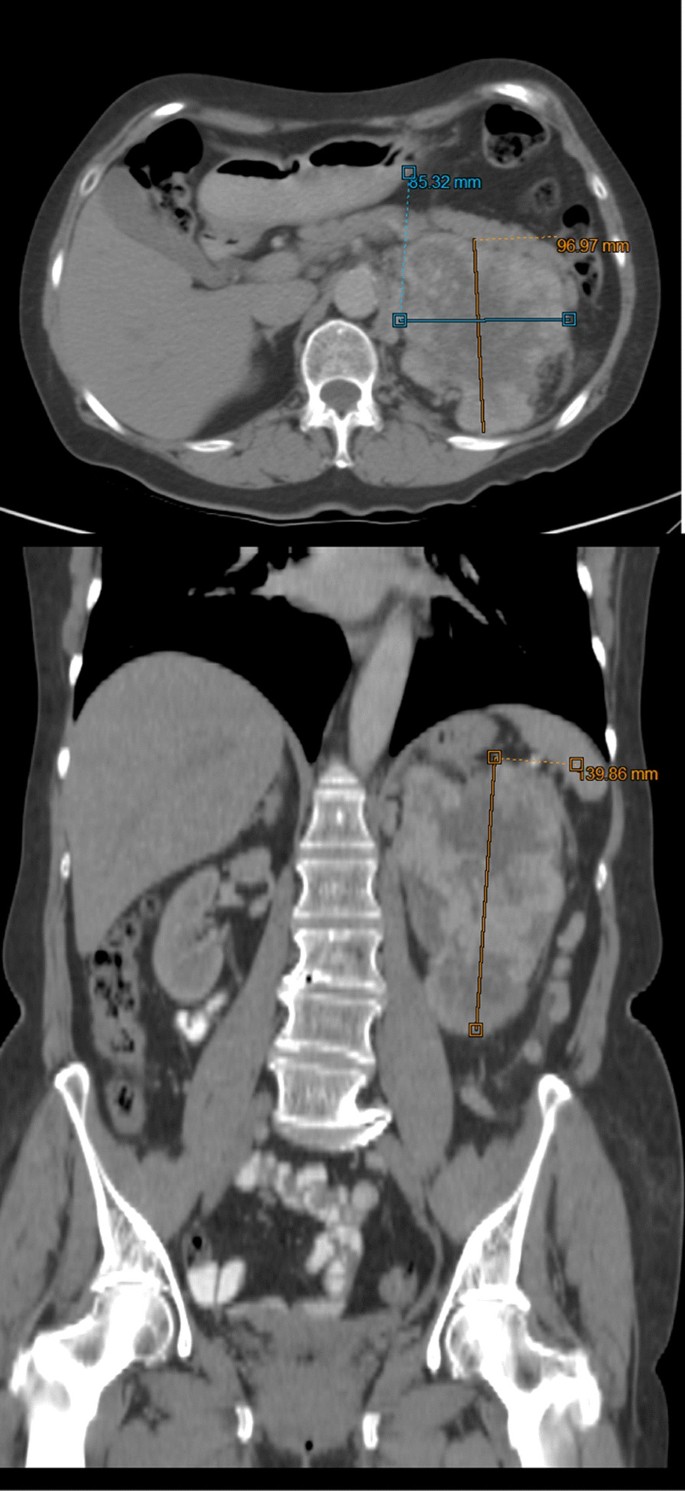

The patient is a 63-year-old Hispanic woman with a history of peptic ulcer disease with dyspepsia and was treated with a proton pump inhibitor (PPI). She was diagnosed with Helicobacter pylori infection and received a triple drug therapy. Subsequently she experienced weight loss of approximately 14 kg over 2 months (BMI = 18.4; previous weight 64 kg, BMI = 23.5), and her dyspepsia did not improve. Colonoscopy and esophagogastroduodenoscopy (EGD) were performed and revealed a 4 cm pyloric ulcer and 70% pyloric stenosis; biopsies were taken at the time of the EGD. The biopsy demonstrated adenocarcinoma in signet ring cells. She was referred to the General Ignacio Zaragoza Regional Hospital Surgery Department for further evaluation. Social history was significant for an 18-pack-year smoking history. Her family history was significant for first-degree relatives with a history of cancer: one with bladder carcinoma and the other with prostate carcinoma. Her physical examination was within normal limits. Laboratory tests demonstrated normal hemoglobin and hematocrit levels, normal liver enzymes, and normal renal function; however, urinalysis was significant for both proteinuria and hematuria, and her blood type is A positive. Carbohydrate antigen (CA)125 and CA19-9 were normal. Her chest X-ray was normal for her age. A computed tomography (CT) scan of her abdomen and pelvis showed a tumor in her left kidney of approximately 140 × 97 × 85 mm with homogeneous enhancement in its upper pole. No distant metastases were evident. Surgical intervention with an exploratory laparotomy was undertaken, where a partial gastrectomy was performed with gastrojejunal anastomosis with omega of Braun reconstruction and left radical nephrectomy. Interoperative cryosections were evaluated by pathology. She had an estimated blood loss of 850 cc, with an estimated surgical time of 210 minutes. The postsurgical course was without complications. The histopathological report describes the left kidney with a size of 100 x 80 mm with a tumor in the upper and middle pole of 70 x 50 mm. The tumor type was clear cell renal cell carcinoma with a histological grade II on the Fuhrman scale with extension beyond Gerota’s capsule. The clinical stage was T4 N0 M0. The gastric tumor with dimensions of 10 × 10 mm in the antrum and pylorus showed diffuse type adenocarcinoma with signet ring cells with little differentiated histological grade and pathological stage T2 N0 M0. The patient is currently under active surveillance with monthly monitoring by the departments of surgery and medical oncology; to date her CT scan and laboratory tests demonstrate no evidence of relapse or distant metastases.